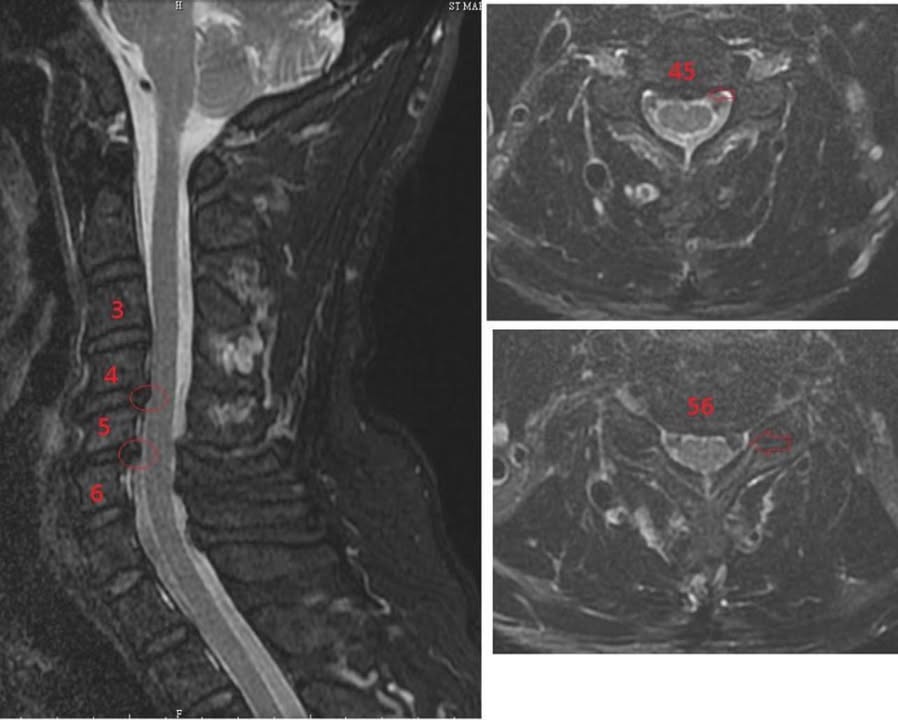

Cervical Spine Treatment Cases 頸椎治療案例 頸椎過直會導致肩膀酸痛嗎?中醫微創針刀療法成功改善頸椎弧度 2021.11.03 頸椎骨刺導致步態不穩、半身麻痛,一定要開刀嗎?中醫針刀治療100天改善實例公開 2021.10.07 冷水刺痛全身、下肢異常竟源自頸椎壓迫?MRI對比揭示非手術療法改善實證 2021.10.08 伏地挺身突然做不到?竟是C6C7頸椎壓迫導致神經肌力減退!中醫微創療法10週改善 2021.09.11 低頭族小心!頸椎滑脫竟導致長期頭痛肩痛與睡眠障礙|12次中醫微創治療成功矯正滑脫 2021.07.16 醫案實證:術後再發的脊髓壓迫症也能靠中醫療法改善 2021.07.10 手術後腳還是麻?頸椎開刀半年症狀未解,靠中醫微創8次改善右腳無力與手麻! 2021.06.30 狂送急診四次竟查不出病因!胸悶心悸原來是頸椎壓迫,靠針刀微創13次改善 2021.06.09 後縱韌帶鈣化壓迫脊髓!步態不穩、手腳麻木竟可逆轉?14週22次針刀治療真實見證 2021.05.06 什麼是中樞型脊髓型頸椎病?症狀、診斷與治療全解析 2021.05.28 神經根型頸椎病症狀解析:肩麻、手痛與肌肉萎縮 2021.04.16 嚴重心悸胸悶竟是頸椎問題!交感神經型頸椎病針治2次症狀明顯改善|真實病例與患者疼... 2021.04.07 從心悸胸悶到手麻夜痛難眠,她竟是頸椎壓迫!真實MRI對比見證中醫逆轉勝療效 2021.04.04 從手腳無力到步態不穩,他竟是頸椎脊髓型壓迫!三個月密集針刀療法逆轉勝|台北蔡大哥... 2021.03.31 頸椎椎間盤突出要一次動四節嗎?手術vs.保守治療完整解析 2021.03.27 ← 上一頁 2 3 4 5 6 下一頁 →